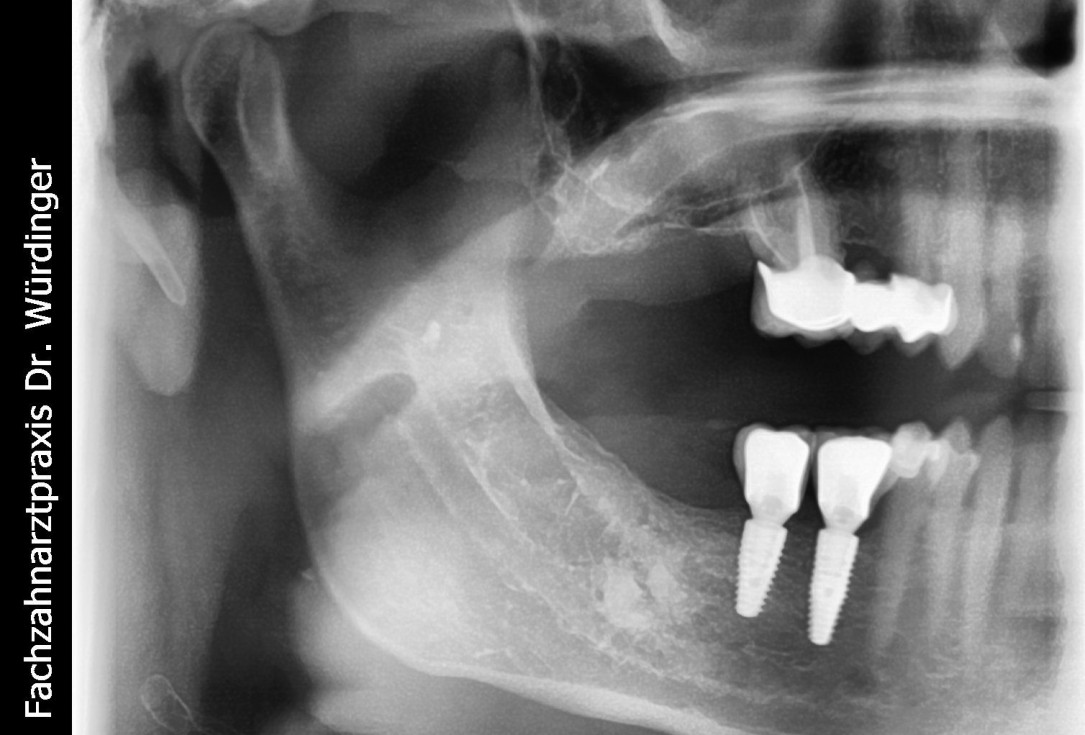

21/28 - X-ray scan of the augmented ridge after implantationThree-dimensional augmentation with maxgraft® cortico - Dr. R. Würdinger